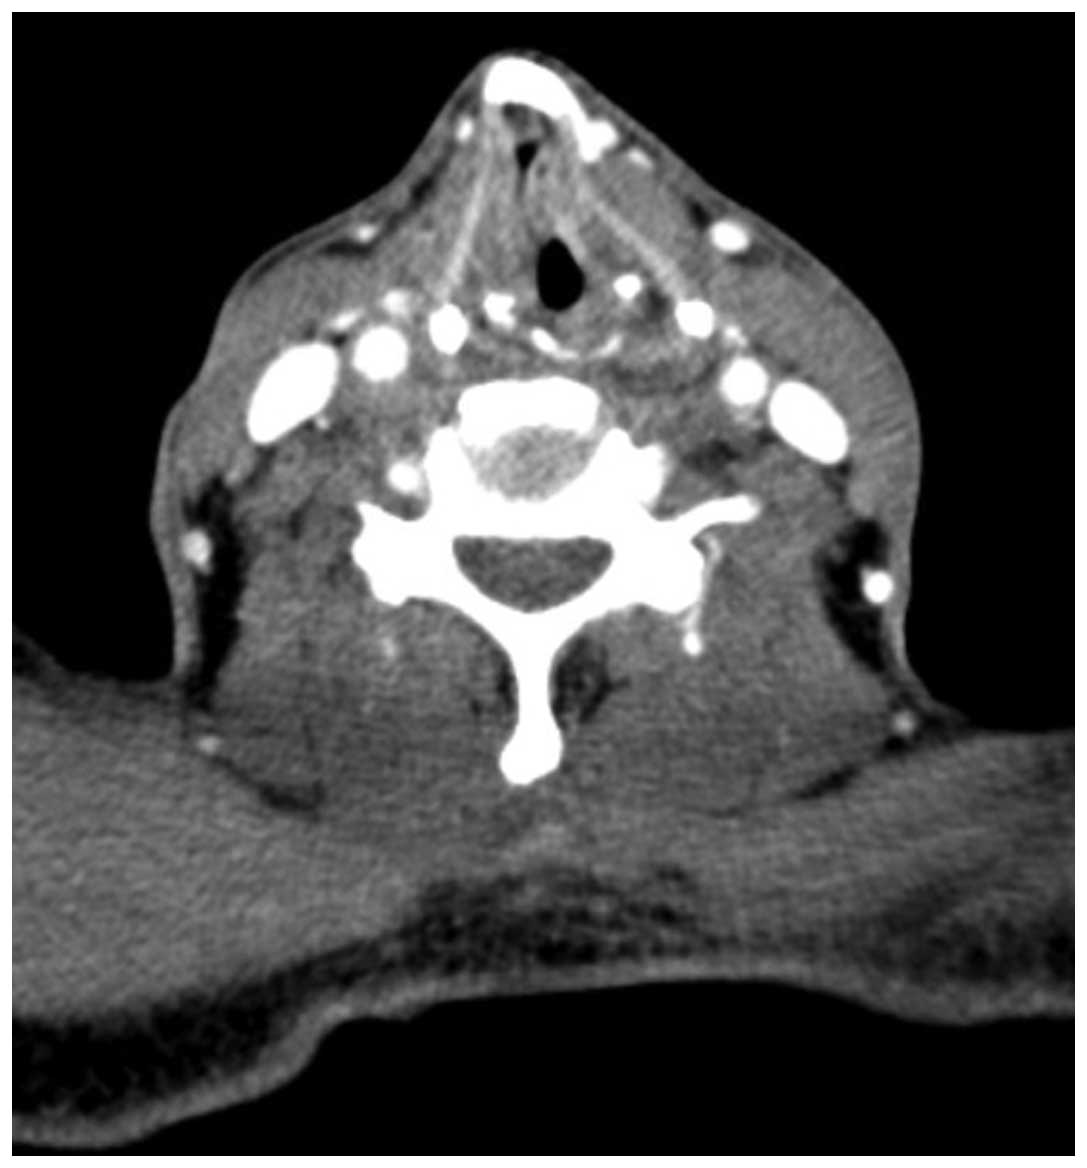

A 55-year-old male was admitted to the Department of Otolaryngology and Head and Neck Surgery, Sir Run Run Shaw Hospital, Medical College of Zhejiang University (Hangzhou, China) complaining of a mass on the left side of the neck, which had been present for six months. The patient reported that the mass had increased rapidly over the two preceding months. The patient stated there was no tenderness or paresthesia, however, the mass had been punctured and pus had been extracted at the Jiangshan Beilin Hospital (Jiangshan, China). An endoscopy revealed a 1.5-cm submucosal mass in the left pyriform sinus, which extended to the lateral wall (Fig. 1). The posterior pharyngeal wall, vocal cords, subglottic region and the base of the tongue appeared to be healthy. Computed tomographic (CT) examinations demonstrated a soft tissue mass in the left pyriform sinus and a 4.4×4.1-cm lesion, which was not well defined from the surrounding healthy soft tissue on the left side of the neck (Fig. 2).